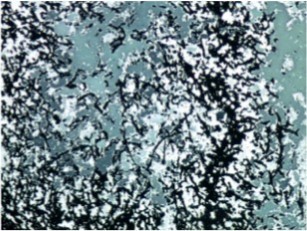

A 64-year-old lady presented to the outpatient department with complaints of headache and right eye blurring of vision for one month. Neurological examination revealed that bitemporal hemianopsia and impairment of visual acuity. Findings from fundus examination were within normal limits. Rest of the brain appeared unremarkable. Endocrine evaluation was normal. Results of renal function tests, liver function tests and haemogram test were within normal limits. A clinical diagnosis of non-secretory pituitary adenoma was made. Magnetic resonance imaging showed a well-circumscribed contrast-enhancing lesion in the sella (Figure 1, Figure 2). The patient underwent an endoscopic endonasal/transsfenoidal surgery in the supine position and total lesion resection was peformed. Intraoperatively, the lesion was found to be yellow colour, soft and avascular and it was removed totally until the sella turcica was visualized (Figure 3).In histopathologic examination septate hyphae were observed between inflammatory cells, Grocott staining is positive, but acid-fast stain for acid-fast bacilli (AFB) was negative. Histopathological findings suggest that infection of Actinomyces (Figure 4, Figure 5). We performed to patient consulted by patients to infectious diseases clinic. Patients underwent intravenous 6x2 gr ampicillin for four weeks.Then oral 4X500 mg amoxicillin treatment is planned a for at least 6 months. Patient did not have any deficits in the next six months.

Figure 4.Light Green PAS stain with filamentous branching bacteria at 10x magnification

In order to isolate actinomyces species from clinical specimens need anaerobic processing and provision for a long time for this reason some paints such as gram staining and Grocott filamentous sulfur granules and silver staining are more preferred according to culture for diagnosis 9. Acid-fast stainig not useful in differentiation of actinomyces species from nocardiosis 10.